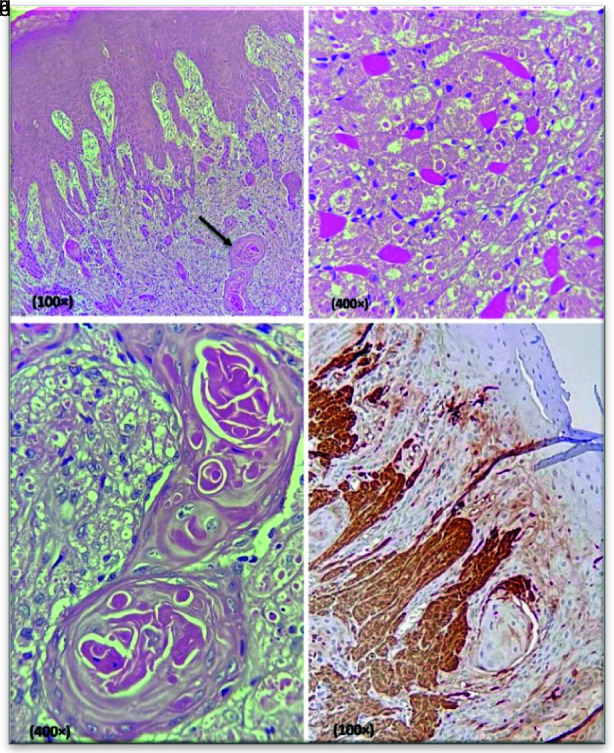

颗粒细胞瘤(GCT)是一种不常见的良性间叶肿瘤,起源于许旺细胞。最常见的部位是舌背。它明显倾向于发生在女性身上,在成年患者中更为常见。GCT 通常表现为无症状、生长缓慢的单个结节。从组织病理学角度看,它显示出多角形细胞的增生,细胞质呈颗粒状,穿透邻近的肌肉。在某些病例中,其上覆盖的上皮表现为假上皮细胞增生(PEH),这可能会使其精确诊断复杂化,并可能与鳞状细胞癌(SCC)相仿。本文介绍了一名 58 岁女性的病例,主诉为舌背无痛性肿块两年。病变呈粉红色,周缘坚实,大小为 1×1 厘米。病变表面完好无损。显微镜检查显示,未包被的大片状多角形细胞,具有丰富的嗜酸性颗粒状胞质和泡状核。覆盖的上皮细胞显示出丰富的 PEH 和角蛋白珠形成。S100 蛋白呈弥漫性阳性。诊断结果为口腔 GCT。虽然 GCT 是一种非侵袭性病变,但由于其表面有大量的 PEH 和角蛋白珍珠形成,可能会与 SCC 相混淆。尽管PEH在口腔病理学家中是一个被忽视的话题,但它在研究领域却具有重要意义。由于它们会模仿其他病变,因此诊断有时会很困难。PEH 的发病机制仍不确定。因此,熟悉这些特征并确定 PEH 的病因有助于正确治疗。本文旨在提高口腔病理学家对口腔病变中的 PEH 的认识。

A granular cell tumor (GCT) is an unusual benign mesenchymal neoplasm with Schwann cells origin. The most common site is the dorsum of the tongue. It has a striking tendency to occur in females and is more frequent in adult patients. GCT typically shows an asymptomatic, slow-growing, single nodule. Histopathologically, it reveals a proliferation of polygonal cells with granular cytoplasm penetrating the adjacent muscles. In some cases, the overlying epithelium demonstrates pseudoepitheliomatous hyperplasia (PEH), which can complicate its precise diagnosis and may mimic squamous cell carcinoma (SCC). This paper presents a 58-year-old woman with a chief complaint of painless mass on the dorsal of the tongue for two years. The lesion was pink and circumscribed with firm consistency measuring 1×1cm. The surface of the lesion was intact. Microscopic examination demonstrated unencapsulated sheets of large, polygonal cells with abundant eosinophilic, granular cytoplasm, and vesicular nuclei. The overlying epithelium showed florid PEH and keratin pearl formation. S100 protein was positive diffusely. The diagnosis of oral GCT was made. Though GCT is a non-aggressive lesion, it may be confused with SCC due to florid PEH and keratin pearl formation. Although PEH is a neglected topic among oral pathologists, it is of great importance in the field of research. Diagnosis can sometimes be problematic because they mimic other lesions. The pathogenesis of PEH is still uncertain. Therefore, familiarity with these characteristics and determining the cause of the PEH leads to correct treatment. This article intends to raise the insight of oral pathologists about PEH in oral lesions.